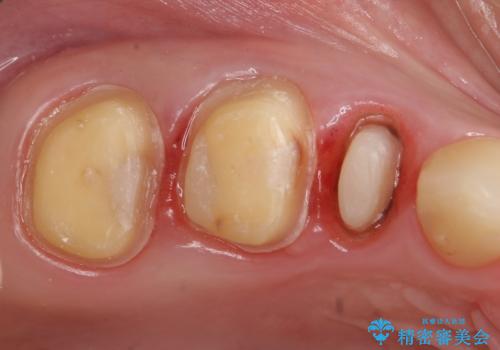

- 他院にて右上5番目の歯の根管治療を行っていたが、痛みが引かないため当院にいらっしゃった方の症例です。

右上5は再根管治療を行い症状の緩解を確認後、オールセラミッククラウンによる補綴を行いました。

右上6、7番目の歯もしみるとのことだったので古い樹脂及び虫歯を除去後、オールセラミッククラウンによる補綴を行いました。

※右上5は歯肉縁下まで虫歯だったため歯冠長延長術を提案しましたが、希望されませんでした。